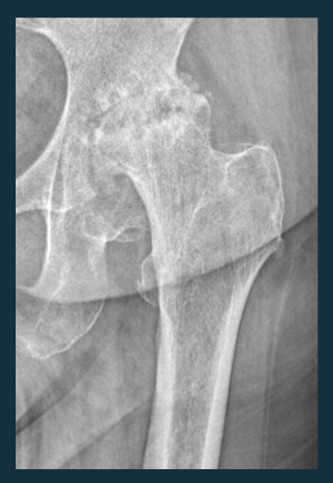

Koksartroz kalça eklemindeki kıkırdakların zamanla aşınması ve hasar görmesi durumudur. Koksartroz genellikle ağrı, sertlik, eklemde kısıtlılık ve hareket zorluğu gibi belirtilerle kendini gösterir.

3. Tanı: Koksartroz genellikle fizik muayene, röntgen, manyetik rezonans görüntüleme (MRG) gibi görüntüleme testleri ve hastanın semptomlarına dayalı değerlendirmelerle teşhis edilir.